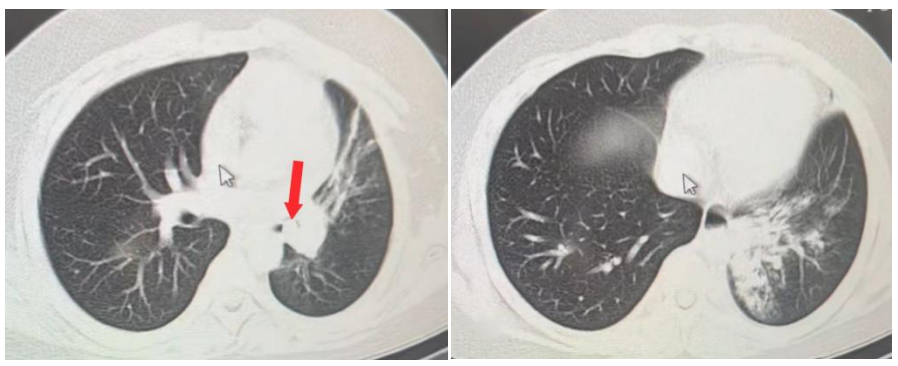

3天前,10岁男孩小宇(化名)一颗牙齿脱落时突发呛咳,当时家长没有给予重视。直到1天前,孩子出现高热(38.8℃)、咳嗽加剧,当地医院胸部CT显示:左肺下叶支气管内致密影,局部炎症并肺实变,诊断为支气管异物合并肺炎。

张艳丽、小儿呼吸内科二病区副主任朱志杰熟练操控支气管镜,一切有条不紊、井然有序,镜下可见:脱落的牙齿被增生肉芽紧紧包裹,牢牢嵌顿在左主支气管远端,且不时有脓液从异物下方涌出,团队成员沉着应对,先精准钳除部分肉芽组织,松动异物,最终用异物钳完整取出牙齿。随后,团队为患儿进行肺泡灌洗,清除左肺脓性分泌物,并对增生的肉芽组织实施冷冻治疗。